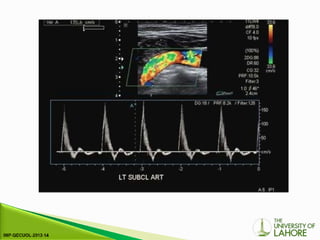

2-13.Transducer position for examination of the

axillary artery and subclavian artery

2-13.Transducer position forexamination of the axillary artery and subclavian artery